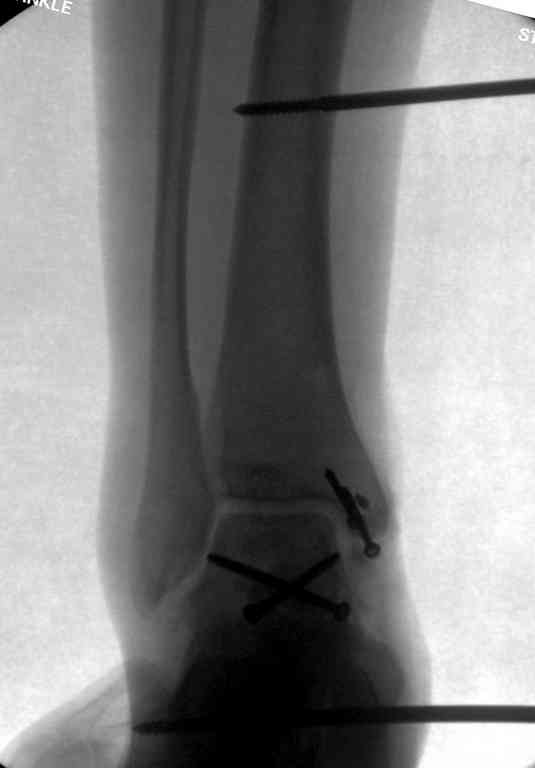

Здесь на фото примеры:

Переломовывих тарана с повреждением медиальной стороны. Через 4 часа после поступления проведена репозиция и фиксация тарана после Irrigation&Debridment. Частичное несращение медиальной лодыжки не беспокоит, вернулся к активному образу жизни. Полная нагрузка разрешена через 11 недель. Финальные снимки через 11 месяцев.

Второй случай прооперирован вчера.

10 дней назад поступил с открытым повреждением медиальной лодыжки и переломо вывихом таранной кости. Ургентно сделана репозиция с наложением наружного фиксатора + Irrigation&Debridment.

Во время репозиции выявили повреждение заднего сухожилия м. тибиалис и задней большеберцовой артерии. Медиальную рану удалось закрыть частично и установлен вакуум.

Дважды провели Irrigation&Debridment с заменой вакуума.

Вчера провели фиксацию.

Из-за многооскольчатости дистальной части малоберцовой, где невозможно было провести фиксацию шурупами, перелом зафиксирован подпирающей пластиной, которая должна служить дополнением отсутствующей дистальной части малоберцовой (lateral cortex substitute).

Для стабильности два шурупа на синдесмоз.

Медиальную рану с приближенными краями продолжаем вакуумировать (KCI). Наружный фиксатор оставлен на пару недель, надеюсь, небольшая рана будет гранулировать и закроется без кожной пластики. Фиксация медиальной ложыжки не планируется.